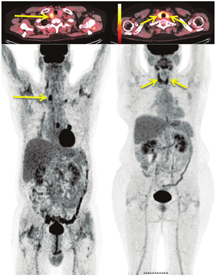

(2)结节性甲状腺肿患者18F-FDG PET/CT检查。在所有18F-FDG显像中,有1%~2%的偶发瘤——在因与甲状腺无关的原因行18F-FDG PET/CT显像时(通常在非甲状腺癌患者中)被发现甲状腺显像剂摄取增加。观察到2种18F-FDG摄取模式,分别为弥漫性和局灶性(图4)。甲状腺弥漫性摄取18F-FDG通常与自身免疫性甲状腺炎有关,几乎没有临床意义[30,31,32]。甲状腺局灶性摄取18F-FDG可见于结节性甲状腺肿,这些偶然发现的结节中约有35%是甲状腺癌[33]。因此,对这些病例应行进一步的检查,以明确结节的性质[34]。在PET/CT显像中意外发现甲状腺肿瘤并不是只有18F-FDG能做到,通过其他的PET肿瘤显像剂也能观察到,例如18F-氟胆碱、68Ga- 1,4,7,10-四氮杂环十二烷-1,4,7,10-四乙酸-苯丙氨酸1-酪氨酸3-奥曲肽(1,4,7,10-tetraazacyclododecane-1,4,7,10-tetraacetic acid(D)-Phe 1-Tyr3-octreotide, DOTATOC)和68Ga-前列腺特异膜抗原配体(图5)[35,36,37]。